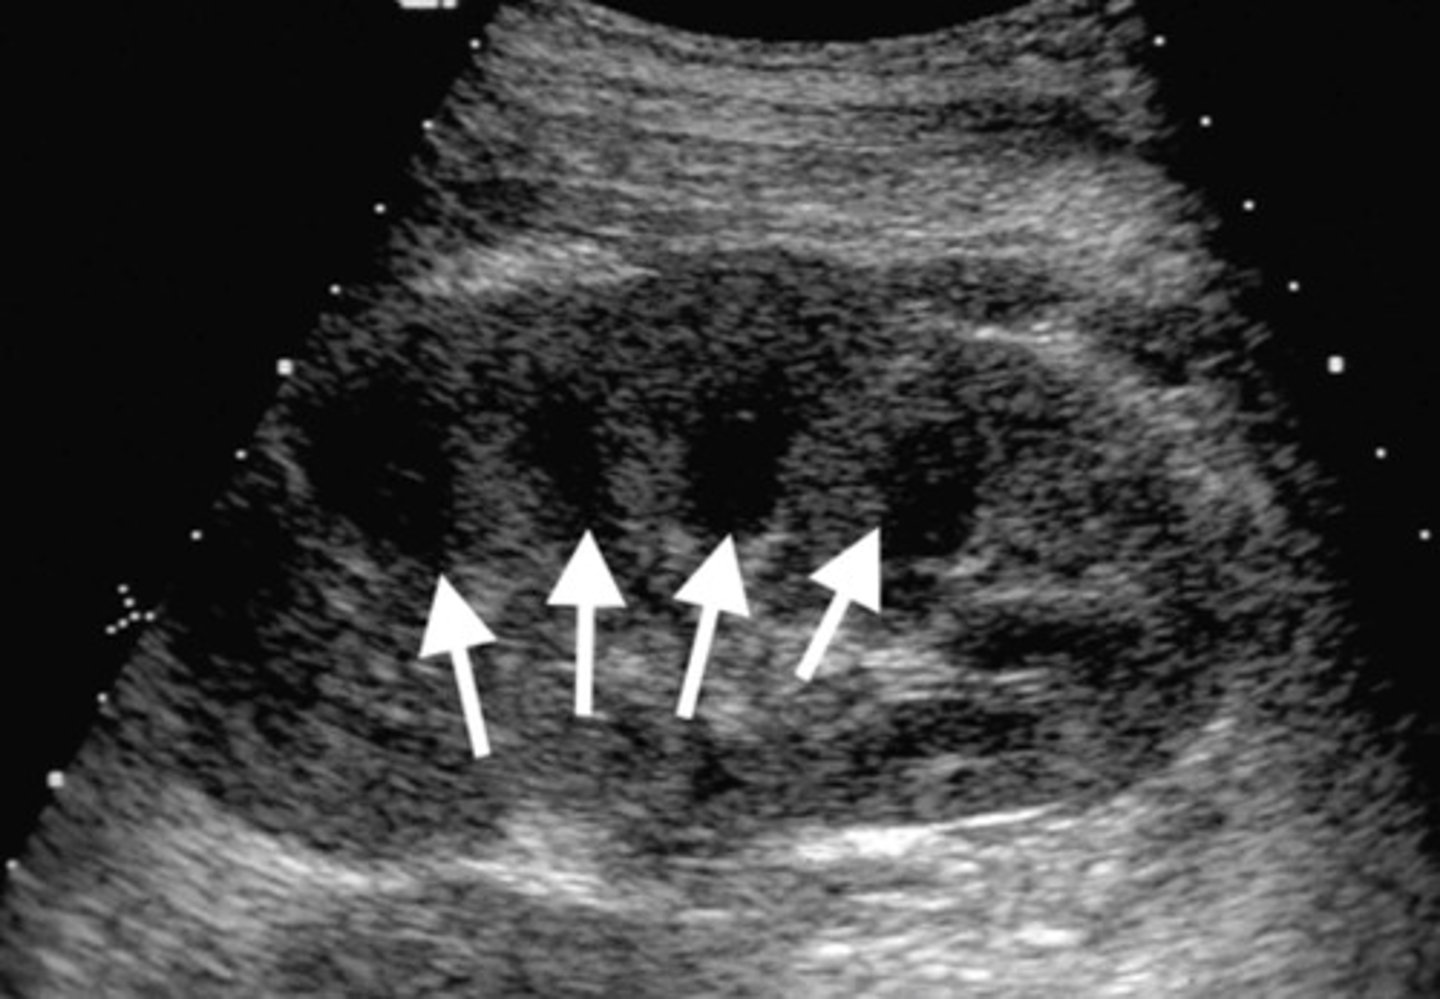

Appearance of Acute Tubular Necrosis (ATN)

Enlarged kidney

Loss of corticomedullary boarders

Appearance of Acute Transplant Rejection

Loss of corticomedullary boarder

Decrease in diastolic flow or flow reversal

RI > 0.8